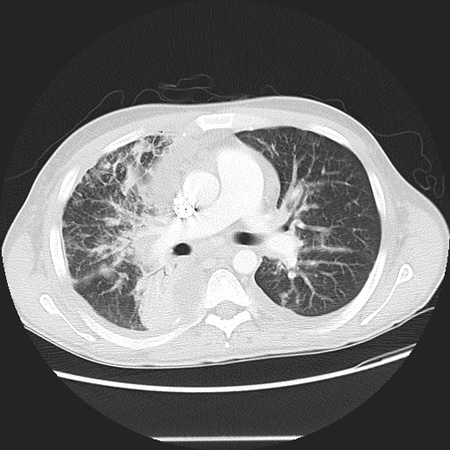

TC do tórax e broncoscopia

Exame

Para estabelecer um diagnóstico de SK pulmonar.Indicadas para os pacientes com radiografia torácica anormal.[2][5]

A biópsia das lesões do trato respiratório é relativamente contraindicada por causa do risco de sangramento.[39][40][41]

Resultado

lesões vasculares características ligeiramente aumentadas na árvore traqueobrônquica, de coloração roxa ou vermelho-cereja

A TC pode ser útil para avaliar SK isceral e nodal profundo, além de lesões ósseas. As lesões ósseas são mais facilmente detectadas por TC e ressonância nuclear magnética (RNM), pois elas frequentemente passam desapercebidas nas radiografias simples ou cintilografias ósseas.[43][Figure caption and citation for the preceding image starts]: Tomografia computadorizada (TC) do tórax mostrando um padrão reticular devido ao comprometimento pulmonar por sarcoma de KaposiDo acervo de Dr. Bruce J. Dezube; usado com permissão [Citation ends].